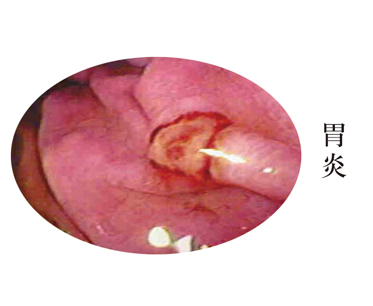

费用始终是患者比较关心的问题,而关心费用的前提先必须是可以治疗自己的疾病。选择一家有资质的胃肠病医院是给自己大的保障,不仅治好胃炎,而且可以避免反复治疗不痊愈造成的金钱浪费。那么,在胃肠病医院治疗胃炎需要多少钱呢?

彻底根除胃炎才是省钱的方式,反复发作只会更花钱,关键是要选择正规的医院接受检查治疗。

胃炎治疗费用受医院水平、地区因素和患者的病情程度影响,并没有一个确定的标准。